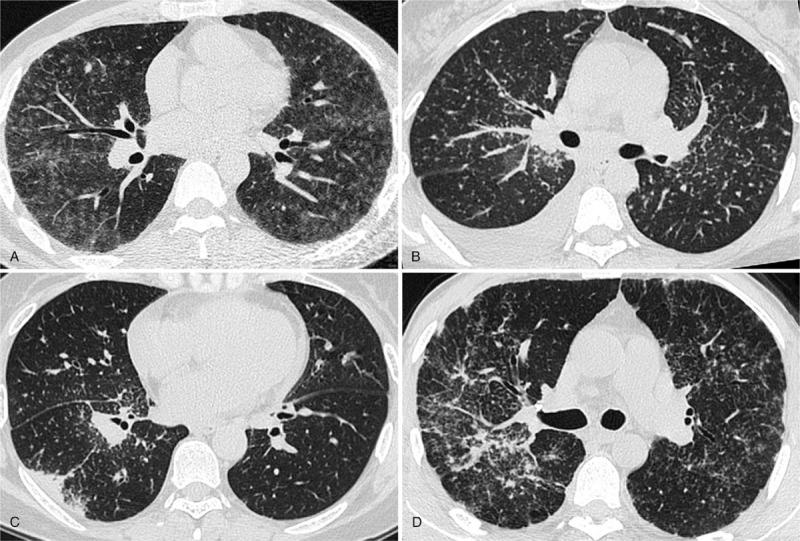

To address the reliability of CT activity score (CTAS) and investigate the relationships between CTAS, lung function changes after treatment and the serum angiotensin-converting enzyme (SACE) levels.Fifty-seven sarcoidosis patients underwent chest high-resolution CT (HRCT) and spirometry, as well as SACE examination, were retrospectively analyzed. Follow-up spirometry in each patient was obtained about 6 months after the initial spirometry. The correlations between CTAS and pulmonary function changes were evaluated by Spearman correlation analysis. According to SACE status, patients were divided into normal and high level 2 subgroups. Comparisons of pulmonary function parameters, HRCT abnormalities extent scores between SACE normal and high 2 subgroups were performed with the Mann-Whitney U test or Independent samples t test.CTAS demonstrated significant correlations with lung function changes (Δ%VC: ρ= 0.543, P < .001; ΔFEV1.0/FVC:ρ = 0.417, P = .001; Δ%TLC: ρ = 0.309, P = .019). In addition, worse initial lung function, larger changes of lung function, and higher extent scores of HRCT were observed in SACE high-level subgroup.The findings of this study suggest that CTAS of initial HRCT is a promising index for disease activity in pulmonary sarcoidosis to some degree. Prospective studies with large cohort designed to address further verification are warranted before wide clinical practice.

为了评估CT活动评分(CTAS)的可靠性,并研究CTAS、治疗后肺功能变化与血清血管紧张素转换酶(SACE)水平之间的关系。对57例结节病患者进行回顾性分析,这些患者均接受了胸部高分辨率CT(HRCT)、肺功能测定以及SACE检查。每位患者在首次肺功能测定后约6个月进行随访肺功能测定。采用Spearman相关分析评估CTAS与肺功能变化之间的相关性。根据SACE状态,将患者分为正常和高水平2个亚组。采用Mann-Whitney U检验或独立样本t检验对SACE正常和高水平2个亚组之间的肺功能参数、HRCT异常程度评分进行比较。CTAS与肺功能变化显著相关(Δ%VC:ρ=0.543,P<0.001;ΔFEV1.0/FVC:ρ=0.417,P=0.001;Δ%TLC:ρ=0.309,P=0.019)。此外,SACE高水平亚组患者的初始肺功能更差、肺功能变化更大、HRCT异常程度评分更高。本研究结果表明,初始HRCT的CTAS在一定程度上是肺结节病疾病活动的一个有前景的指标。在广泛临床应用之前,有必要进行大规模队列的前瞻性研究以进一步验证。